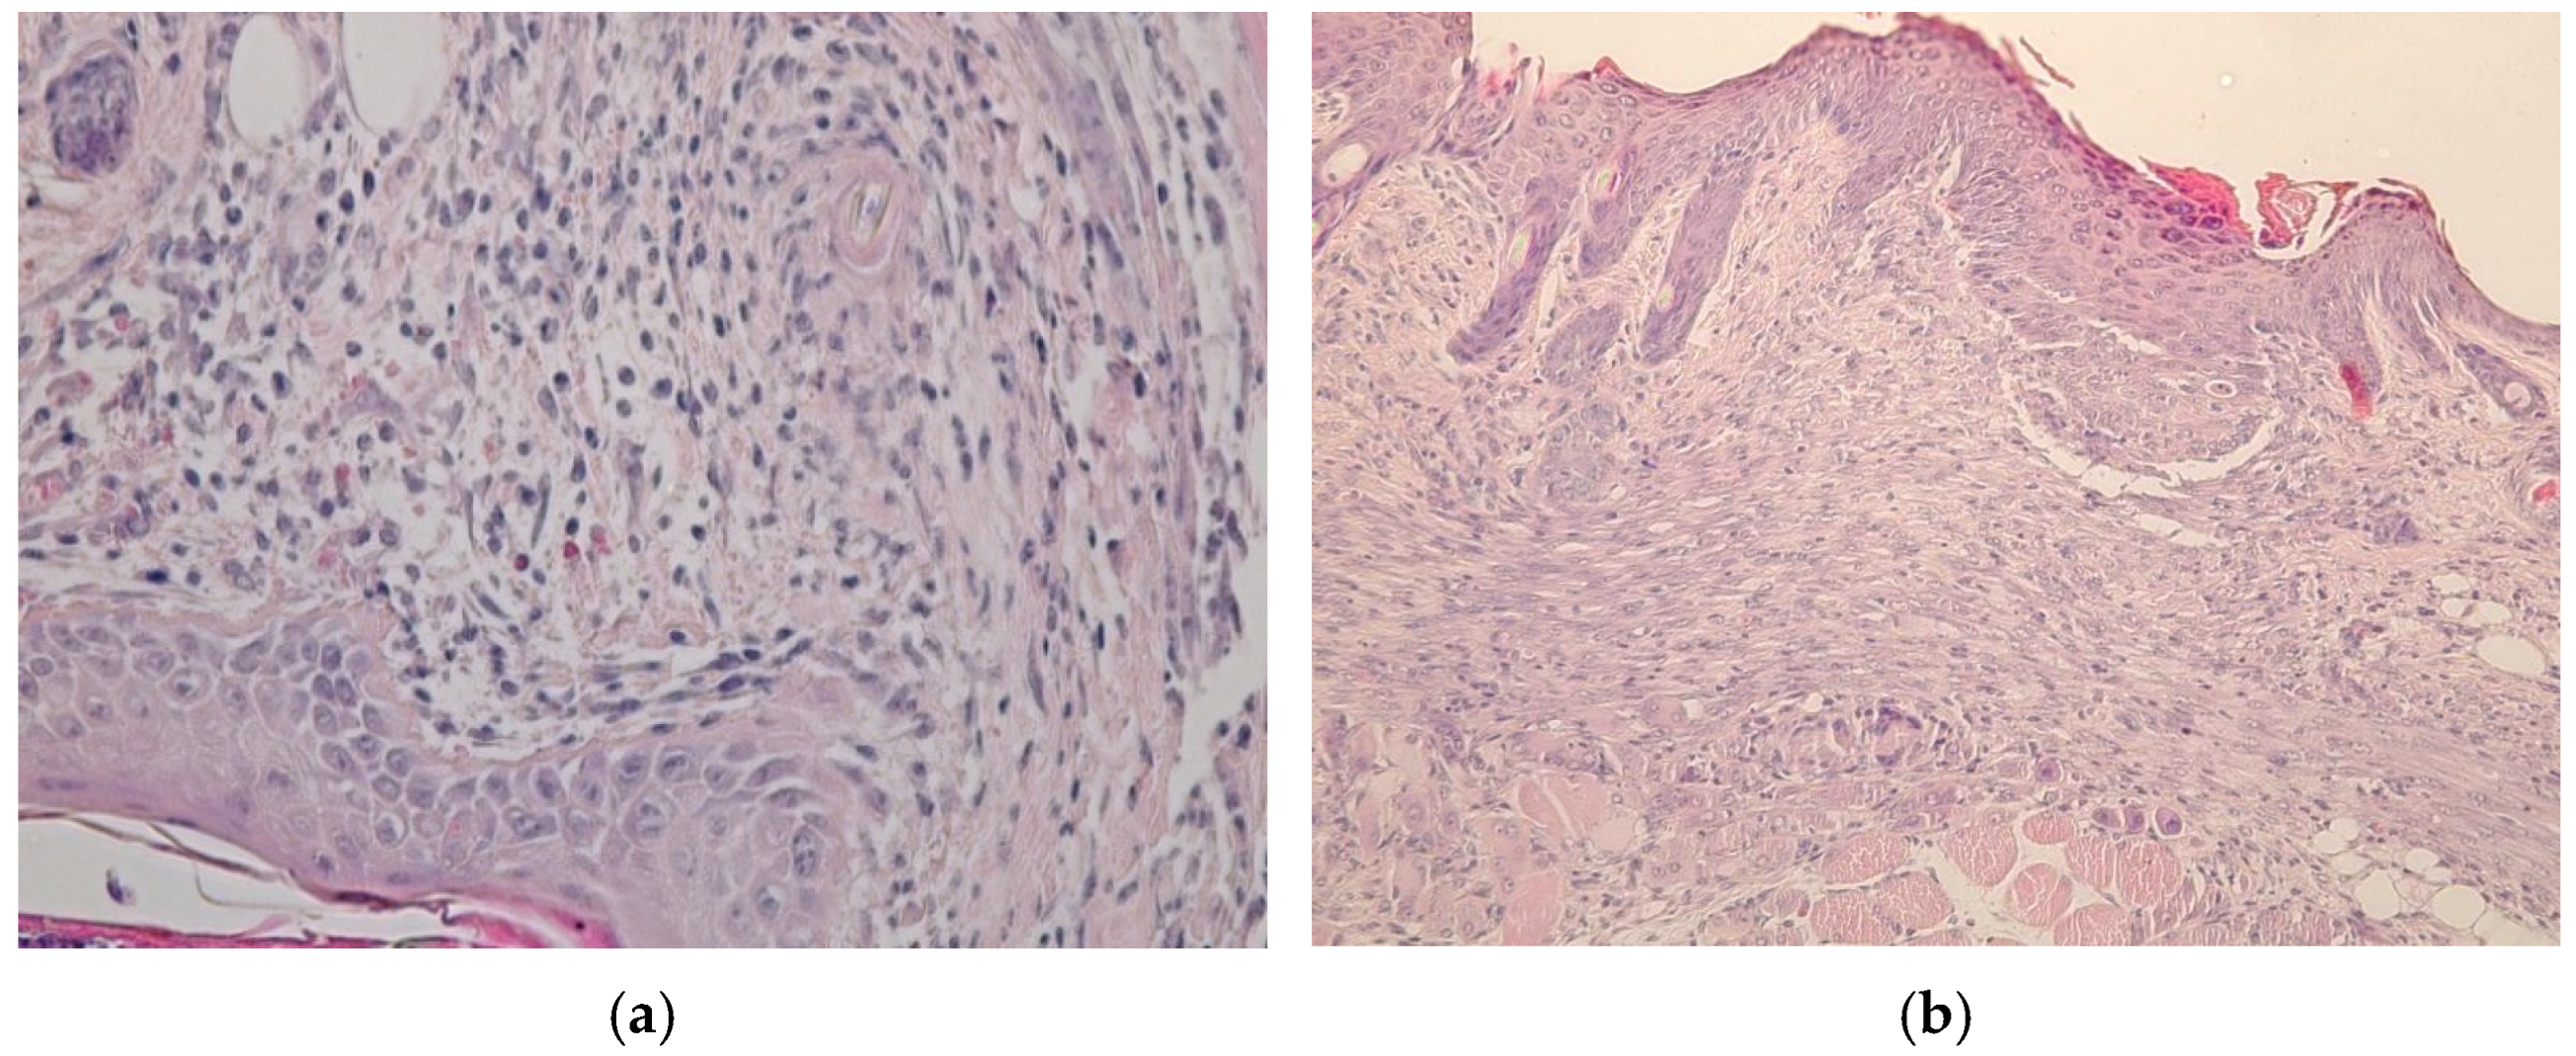

4.6. Investigation of Wound-Healing Ability of ZnO NPs Gels

4.7. Histological Research

- (1)

- A group treated with a gel of ZnO MPs and hydroxyethyl cellulose (control group);

- (2)

- A group treated with a gel of ZnO NPs modified with hydroxyethyl cellulose (experimental group).